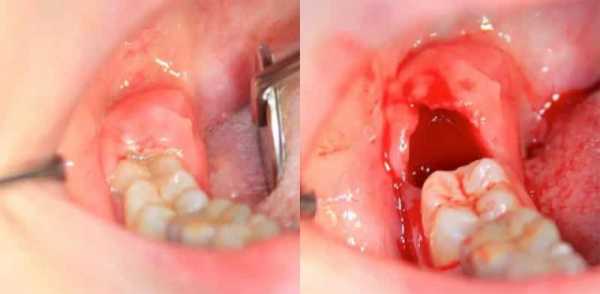

Удаление зуба, по своей сути – это операция. И она сопровождается кровотечением, как любая другая. Это первичное кровотечение. Через несколько минут после удаления кровь свертывается и кровотечение прекращается. Но в некоторых случаях оно продолжается, вот о таких случаях я вам и расскажу.У некоторых больных наступает вторичное кровотечение, оно обусловлено влиянием адреналина, который…

Осложнения после удаления зуба

Как правило, хирургическое вмешательство заканчивается положительным эффектом. Но, бывают ситуации, при которых пациент испытывает ощущение дискомфорта в течение длительного времени после проведенной операции: боль не утихает, преследует гнилостный запах.

Это случается по нескольким причинам:

- не происходит образования сгустка крови в лунке;

- в канале осталась часть корня;

- воспаление надкостницы (после занесения инфекции).

Очень часто бывает быстрое отторжение сгустка, что приводит к засорению канала. Случается так, что человек не учитывает рекомендации врача. Сразу после проведения операции, придя домой, начинает полоскать рот, пить или есть. Вследствие этого зубной канал становится незащищенным и уязвимым. Обычно процесс заживления происходит на 2 или 3 день, и поэтому, если в течение недели после удаления зуба боль, опухоль, или дурной запах не исчезают, то необходима помощь врача.